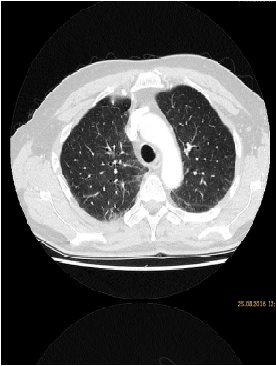

Synchronous Pneumonitis, Hepatitis and Enteritis Under Treatment with PI3kδ Inhibitor Idelalisib for Follicular Lymphoma

Maria Vergoulidou*, Diana Japaridze, Norbert Grobe